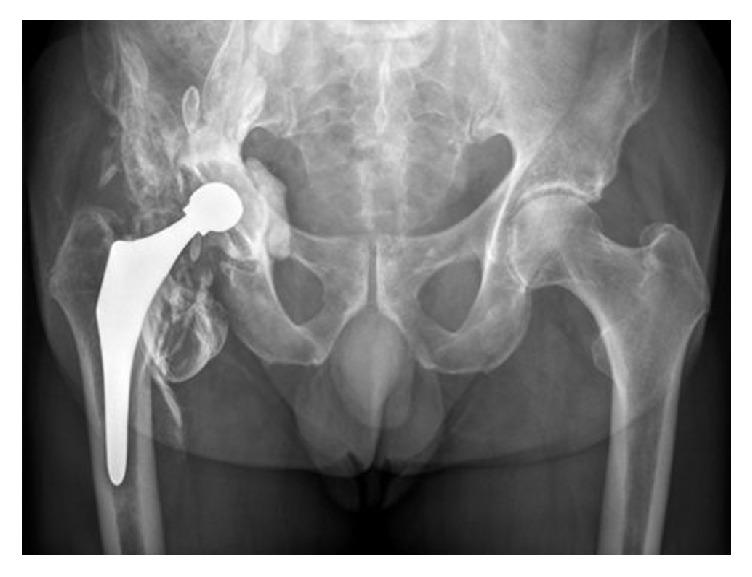

This case illustrates the potential for systemic cobalt toxicity in non-metal-on-metal bearings and its potentially devastating consequences. We present a 71-year-old male with grinding sensations in his right hip following ceramic-on-ceramic total hip arthroplasty (THA). After diagnosing a fractured ceramic liner, the hip prosthesis was revised into a metal-on-polyethylene bearing. At one year postoperatively, X-rays and MARS-MRI showed a fixed reversed hybrid THA, with periarticular densities, flattening of the femoral head component, and a pattern of periarticular metal wear debris and pseudotumor formation. Before revision could take place, the patient was admitted with the clinical picture of systemic cobalt toxicity, supported by excessively high serum cobalt and chromium levels, and ultimately died. At autopsy dilated cardiomyopathy as cause of death was hypothesized. A third body wear reaction between ceramic remnants and the metal femoral head very likely led to excessive metal wear, which contributed systemic cobalt toxicity leading to neurotoxicity and heart failure. This case emphasizes that fractured ceramic-on-ceramic bearings should be revised to ceramic-on-ceramic or ceramic-on-polyethylene bearings, but not to metal-on-polyethylene bearings. We aim to increase awareness among orthopedic surgeons for clinical clues for systemic cobalt intoxication, even when there is no metal-on-metal bearing surface.

该病例说明了在非金属对金属轴承中发生全身钴中毒的可能性及其潜在的灾难性后果。我们报告一名71岁男性,在接受陶瓷对陶瓷全髋关节置换术(THA)后右髋出现磨削感。在诊断为陶瓷内衬骨折后,将髋关节假体翻修为金属对聚乙烯轴承。术后一年,X线和MARS-MRI显示为固定的反向混合型THA,有关节周围密度、股骨头部件扁平,以及关节周围金属磨损碎片和假肿瘤形成的表现。在进行翻修之前,患者因全身钴中毒的临床表现入院,血清钴和铬水平过高支持了这一诊断,最终患者死亡。尸检推测死亡原因是扩张型心肌病。陶瓷残余物与金属股骨头之间的三体磨损反应很可能导致了过度的金属磨损,这导致了全身钴中毒,进而导致神经毒性和心力衰竭。该病例强调,陶瓷对陶瓷轴承骨折应翻修为陶瓷对陶瓷或陶瓷对聚乙烯轴承,而不应翻修为金属对聚乙烯轴承。我们旨在提高骨科医生对全身钴中毒临床线索的认识,即使不存在金属对金属轴承表面。